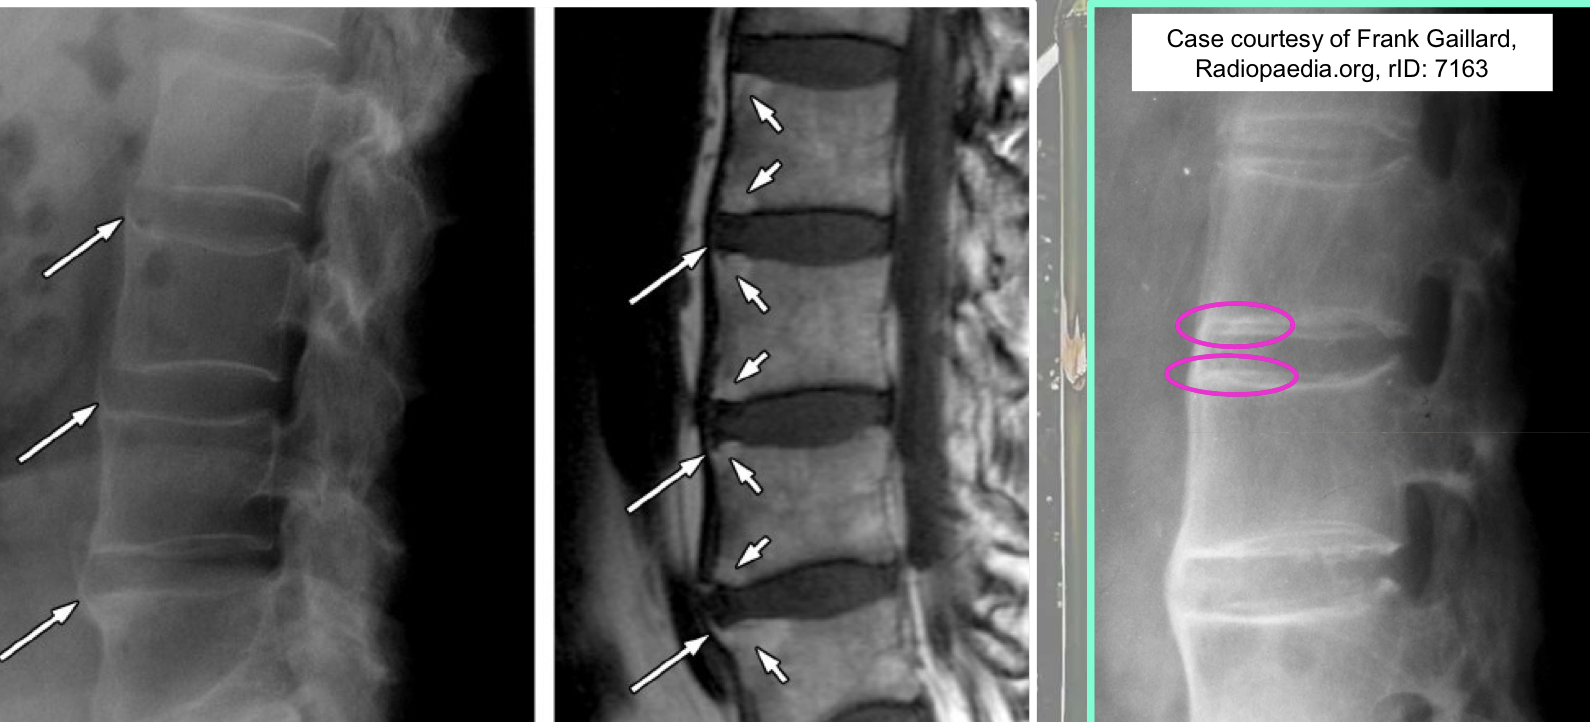

What finding of AS is found in this image

symmetrical, thin, marginal syndesmophytes (bamboo sign)

gracile/fragile

Interspinous ligament ossification (Dagger sign)

Z-joint/facet capsular ossification (Railroad track sign)